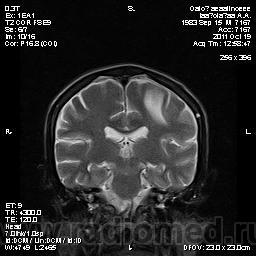

Молодой человек, жалуется только на головные боли и слабость в правой руке и ноге (около месяца).

Пациент полуасоциальный, нельзя исключить анамнез наркоманский....

ППН (включая ячейки пирамидок и сосцевидные отростки) тотально заполнены жидкостным компонентом...

Колеги, спасибо за высказывания. В данном случае про наркоманский анамнез указано не спроста... Есть мнение, что в этом лежит точка отсчета.... По поводу абсцесса и гематомы - не согласен; по поводу первого - нет соответствющей клиники, по поводу второго - не характерна локализация и сигнальные характеристики. Не буду томить общественность касательно собственного мнения. Есть две гипотезы, о которых думается в данном случае: прогрессирующая лейкоэнцефалопатия и новообразование... Но без контраста их не разрешить...